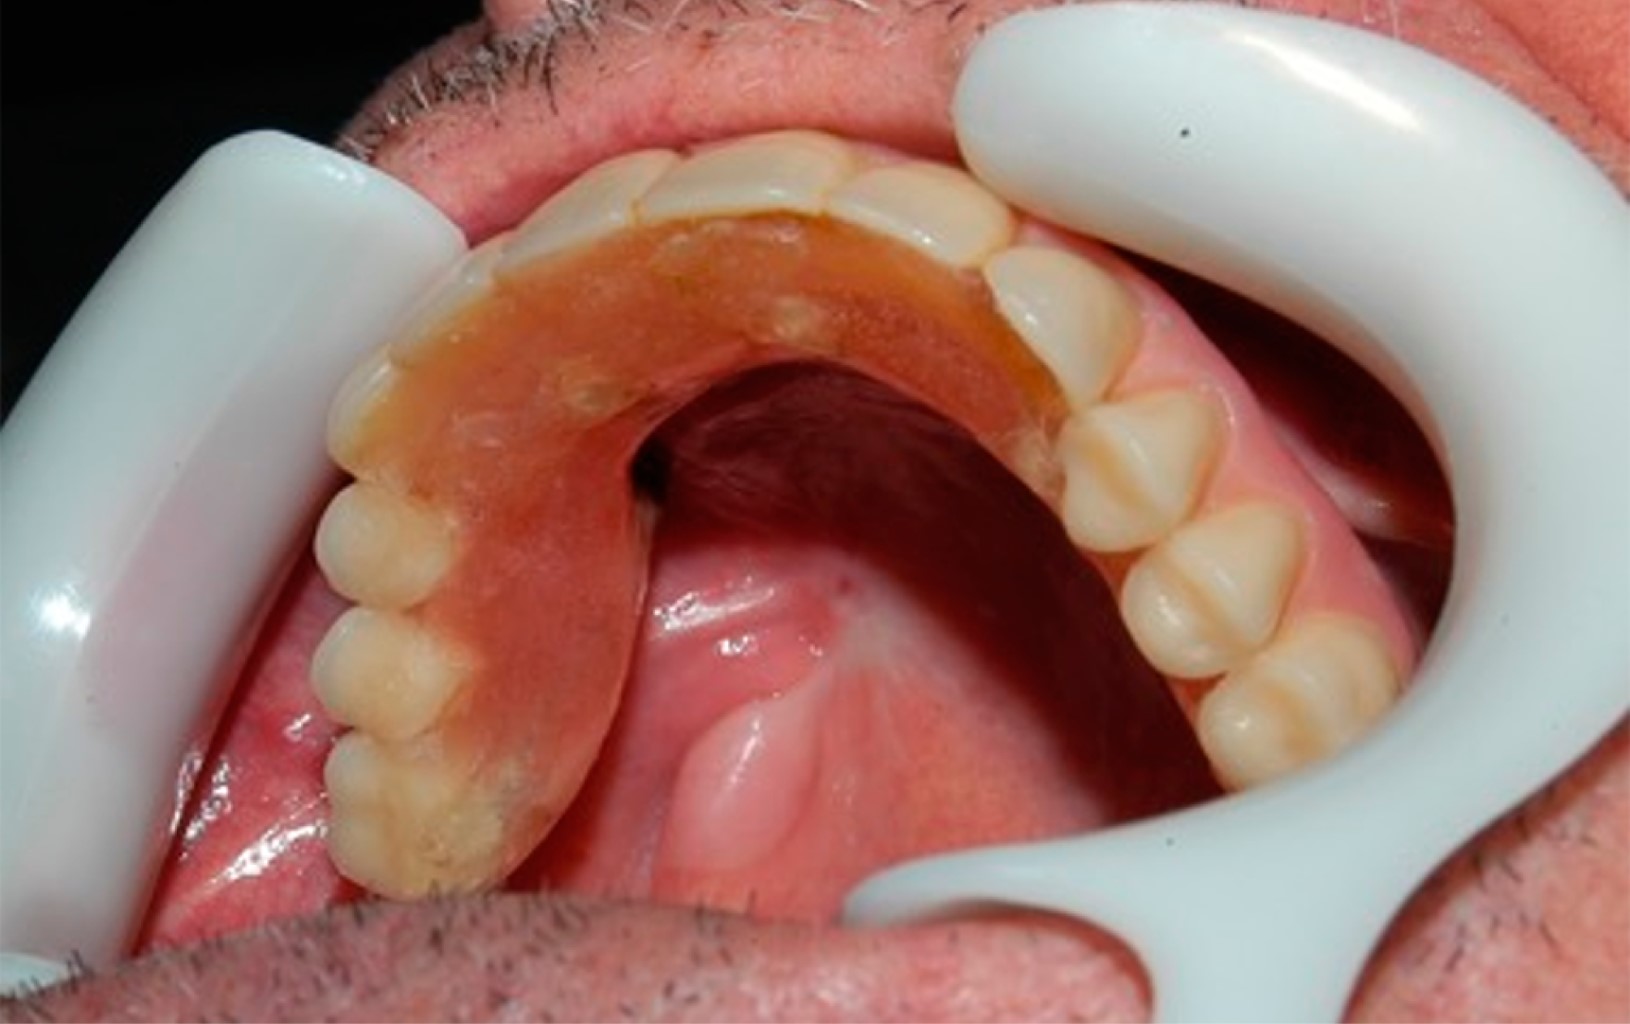

El leiomiosarcoma es un tipo de cáncer que se origina en las células musculares lisas del útero, el tracto gastrointestinal y otros tejidos blandos. La rara aparición del leiomiosarcoma en la cavidad oral se ha correlacionado con la escasez de estructuras musculares lisas en esta localización. Se trata de un tumor de tejidos blandos raro y agresivo que representa aproximadamente 5-10% de todos los sarcomas de tejidos blandos, y sólo 3% de estos tumores se producen en la región de la cabeza y el cuello. El diagnóstico diferencial puede ser problemático. El aspecto físico puede confundirse con afecciones no malignas. El diagnóstico diferencial clínico de la lesión incluye los tumores glandulares (adenoma pleomórfico, carcinoma mucoepidermoide y carcinoma adenoide quístico) y los tumores mesenquimales. Relatamos un caso de leiomiosarcoma maxilar en un paciente de 86 años que fue sometido a una resección tumoral y tuvo como complicación la necrosis casi completa del retallo quirúrgico. Gracias a la terapia con láser, logramos la curación completa del colgajo y el implante y la rehabilitación dental con carga inmediata.

Figura 4